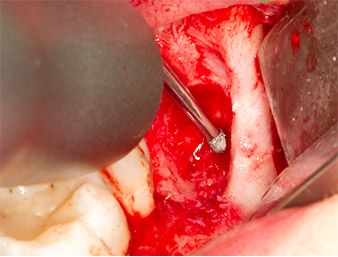

Piezomed B5

Fig. 5: Bone in the region of the alveole is lifted with a chisel-shaped piezo surgical instrument (Piezomed B5). This bone is used as autologous augmentation material after removal of the root remnant (cf. Fig. 13 and 14).

To obtain autogenous material for subsequent wound treatment, healthy bone chips were harvested from the surroundings of the root remnant with a piezo surgical instrument (Piezomed B5) (Fig. 5).

The autogenous tissue was removed with the scraper-shaped section of the working part of the instrument and stored in a physiological saline solution until further use (cf. Fig. 13).

To expose the root remnant with as little trauma as possible to the tissue, a further instrument was used (Piezomed S2) that is primarily indicated for preparing the lateral window in augmentations of the sinus floor. The diamond-coated ball was additionally used to smooth sharp bone edges (Fig. 6 and 7). All the Piezomed attachments were used with the relevant automatic default setting without booster function.